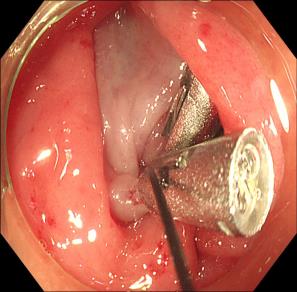

• 可旋转重复开闭软组织夹联合外科尼龙缝合线法闭合结直肠内镜黏膜下剥离术后缺损的临床应用价值

2025, 31(12):77-82. DOI: 10.12235/E20250091

摘要 (77) HTML (65) PDF 1.86 M (64) 评论 (0) 收藏

摘要:目的 探讨可旋转重复开闭软组织夹联合外科尼龙缝合线法(ROLM)闭合结直肠内镜黏膜下剥离术(ESD)后黏膜缺损的临床疗效。方法 回顾性分析2024年1月-2024年6月15例在南京医科大学附属常州市第二人民医院因早期结直肠肿瘤行ESD,并采用ROLM闭合黏膜缺损患者的临床资料。观察患者病灶相关情况(病灶部位、缺损最大径和术后病理)、手术相关情况(术后缺损成功闭合率、钛夹使用数量、ROLM缝合时间和住院时间)、术后并发症发生情况和术后随访情况。结果 术后缺损成功闭合率为100%。病灶长径3.0~6.0 cm,平均(3.7±0.8)cm。缺损部位:回盲部1例,升结肠6例,横结肠肝曲1例,降结肠2例,乙状结肠3例,直肠2例。术后病理为:管状腺瘤8例,黏膜下囊肿1例,管状绒毛状腺瘤5例,胃肠道间质瘤1例。钛夹使用数量为7~20枚,中位数为11(10,13)枚。ROLM缝合时间为13~37 min,平均(19.3±6.5)min。住院时间4~9 d,平均(6.5±1.2)d。术后无出血、穿孔、感染和消化道狭窄等并发症发生。术后3~6个月复查肠镜,手术创面均愈合良好。结论 ROLM能够安全、有效地闭合结直肠ESD后黏膜缺损。值得临床推广应用。